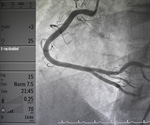

What is an Angiogram?